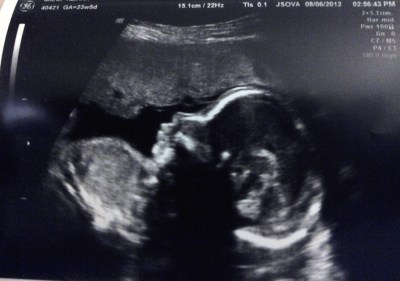

Alle 14.40 appuntamento dalla gine. Picci sta alla grande, la mia placenta comincia ad ispessirsi un po’ e a salire, insomma, va tutto bene.

Non ha un profilo adorabile??